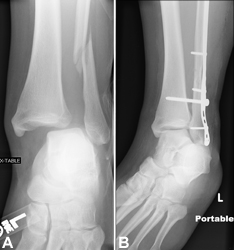

(Left) X-ray of bimalleolar ankle fracture. (Right)Surgical repair bimalleolar ankle fracture